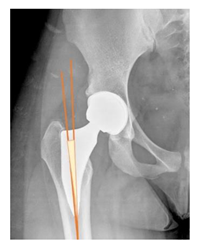

Plain radiographs were evaluated preoperatively and at the most recent follow-up, after appropriate calibration. Positional parameters were assessed according to values guidelines from published literature, as listed in Table 1 [23,24,25,26,27,28,29,30,31]. Femoral stem and acetabular cup osteointegration were quantified according to Engh [32] and Moore scale [33]. Heterotopic ossifications were graded according to the Brooker system [34].

3.4. Radiographic Evaluation

Preoperative and postoperative radiographic data are reported in Table 4. Preoperatively, 18 THR (24.3%) were implanted in skeletally immature children with closed triradiate cartilage (1 ≤ Risser ≤ 3). Radiographic acetabular insufficiency (LCEA < 25° and AI > 13°) was detected in 14 hips (18.9%), while protrusion was present in 3 hips (4.1%) An excessive valgus of the femoral neck was observed in 19 hips (25.7%), while an important varus deformity was present in 7 hips (9.5%).

Postoperative radiographs showed a significant vertical malposition of the cup in 1 case (1.4%), a significant varus stem in 8 cases (10.8%) and a significant valgus stem in 1 case (1.4%). Two patients (2.7%) showed moderate heterotopic bone formation (Brooker ≥ 2), that did not significantly affect the hip motion and symptoms. All those THR that did not undergo revision showed good radiographic osteointegration, with no evidence of implant breakage, radiographic lucencies, bone defects, cup migration, or stem subsidence at the most recent radiographs.

In our experience, implant malposition was the only reason for implant revision. In one case, progressive subsidence was observed in a varus undersized stem, implanted in a boy with Albers–Schömberg disease; in another case, an excessively vertical cup with a 28 mm femoral head caused hip instability and required cup revision.

THR can be a challenging procedure in very young people. The combination of distorted anatomy, small physique, and poor bone stock can impede proper implant placement. Implant sizing may be an issue in these patients. The combination of young age and peculiar conditions such as skeletal dysplasia may require particular attention in preoperative planning and implant selection. Noticeably, we used the smallest size of the cup in 11 hips (15%) and the smallest size of the stem in 14 hips (19%). A meticulous preoperative planning, even using simulation software, [40,41,42] and careful implant selection, sometimes requiring even customized implants [37], is crucial in such conditions, to prevent unpleasant pitfalls during the operation.